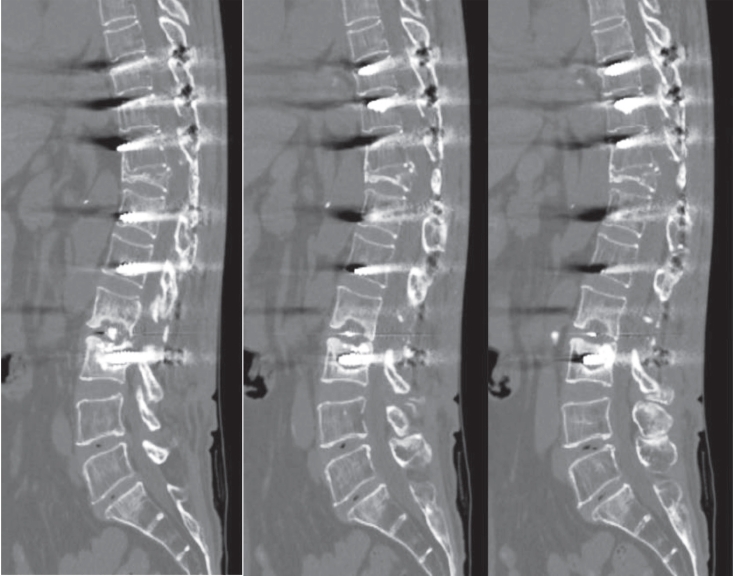

The incidence of mechanical failures was systematically recorded, comparing patients with cement-augmented pedicle screws to those without. Failures were classified into three categories: pull-out, screw loosening, and cage protrusion— the latter defined as displacement of the implanted cage beyond the vertebral body margins (Fig. 3). Fusion status was also evaluated using follow-up radiographs and CT scans. Successful fusion was defined as continuous bone bridging across the intervertebral space without radiolucent lines surrounding the implant. Representative CT images of successful fusion are shown in Fig. 4.

Fig. 3.

(A) Immediate postoperative radiograph showing pedicle screw and cage placement. (B) Follow-up radiograph at two months demonstrating cage protrusion, with the cage extending beyond the vertebral body margins.

Fig. 3. (A) Immediate postoperative radiograph showing pedicle screw and cage placement. (B) Follow-up radiograph at two months demonstrating cage protrusion, with the cage extending beyond the vertebral body margins.